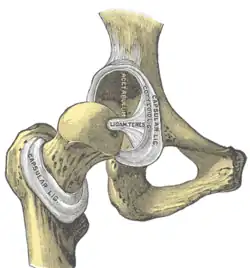

In der Mitte ist das Acetabulum zur Hüftgelenksgrube (Fossa acetabuli) ausgehöhlt. In dieser Grube entspringt ein Band (Ligamentum capitis ossis femoris), das einen dünnen Zweig der Arteria obturatoria, die Arteria capitis femoris, aufnimmt. Diese ist an der arteriellen Versorgung des Oberschenkelknochens beteiligt. Das Band selbst hat keine mechanische Funktion. Die offene Seite des Halbmonds – beim Menschen vorn unten – wird als Incisura acetabuli („Hüftgelenkpfanneneinschnitt“) bezeichnet und durch ein Band (Ligamentum transversum acetabuli) verschlossen.

Der Rand des Acetabulums wird durch eine Gelenklippe (Labrum acetabuli) erhöht, die auf der umgebenden, knöchernen Gelenkpfanne (Limbus acetabuli) aufsitzt, so dass der Kopf des Oberschenkelknochens über seinen Äquator hinaus umfasst wird und daher ein Nussgelenk bildet. Die Gelenklippe (Labrum acetabulare) wird oftmals klinisch allerdings ebenfalls als Limbus bezeichnet.[2]